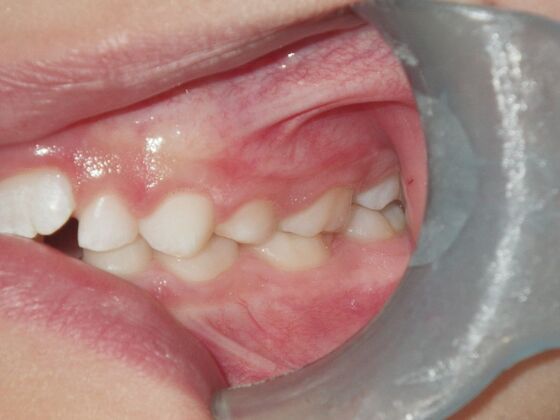

Dylan presented with a functional crossbite in which we used removable expansion appliances for 12 months, followed by bracketing of upper and lower teeth including primary ones to gain alittle more expansion, allowed to wear retainers for 6 months and then followed closely with 6 month ortho recalls and began Phase 2 treatment within 24 months and finished his ortho treatment.